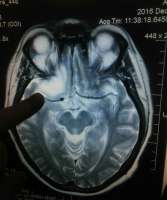

I1Bd2awqlzE.jpg (445Кб, 1559x806)

Великий двощик, поясни пожалуйста за диагноз. Нашли у мамы, вся семья в шоке.

Аноним 06/01/17 Птн 22:37:22  557217

>>557152

На опухоль не похоже, раз контуры чёткие. Может глистная инвазия?

Аноним 06/01/17 Птн 22:39:21  557218

>>557217

>>c чётким неровным контуром. Я не знаю, поэтому прошу консультации здесь.

Аноним 06/01/17 Птн 23:11:33  557228

Для начала возьми диск МРТ и сходи к нормальному нейрохирургу (именно нейрохирургу, не онкологу и не неврологу), чтобы пересмотрел результаты. Дальше он тебе сам скажет, куда идти.

Если ты в Москве, сходи на консультацию в поликлиническое отделение НИИ им. Бурденко.

а симптомы какие?

>>557255

Возник приступ эпилепсии, спутанность сознания.